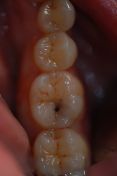

La paziente presenta una lesione cariosa a carico del 4.6 che viene trattata ripulendo accuratamente la cavità dal tessuto carioso e ricostruita la parte mancante attraverso una ricostruzione estetica in materiale composito che ben si mimetizza con il colore dell'elemento dentario. Quando le lesioni cariose vengono intercettate in queste fasi iniziali si riesce a conservare una maggior quantità di tessuto biologico, preservando l'integrità del dente per un maggior periodo di tempo e, naturalmente, anche le spese sono ridotte. Per questo è importante effettuare sempre controlli periodi semestrali dal dentista per poter intercettare i problemi quando ancora sono facilmente risolvibili.